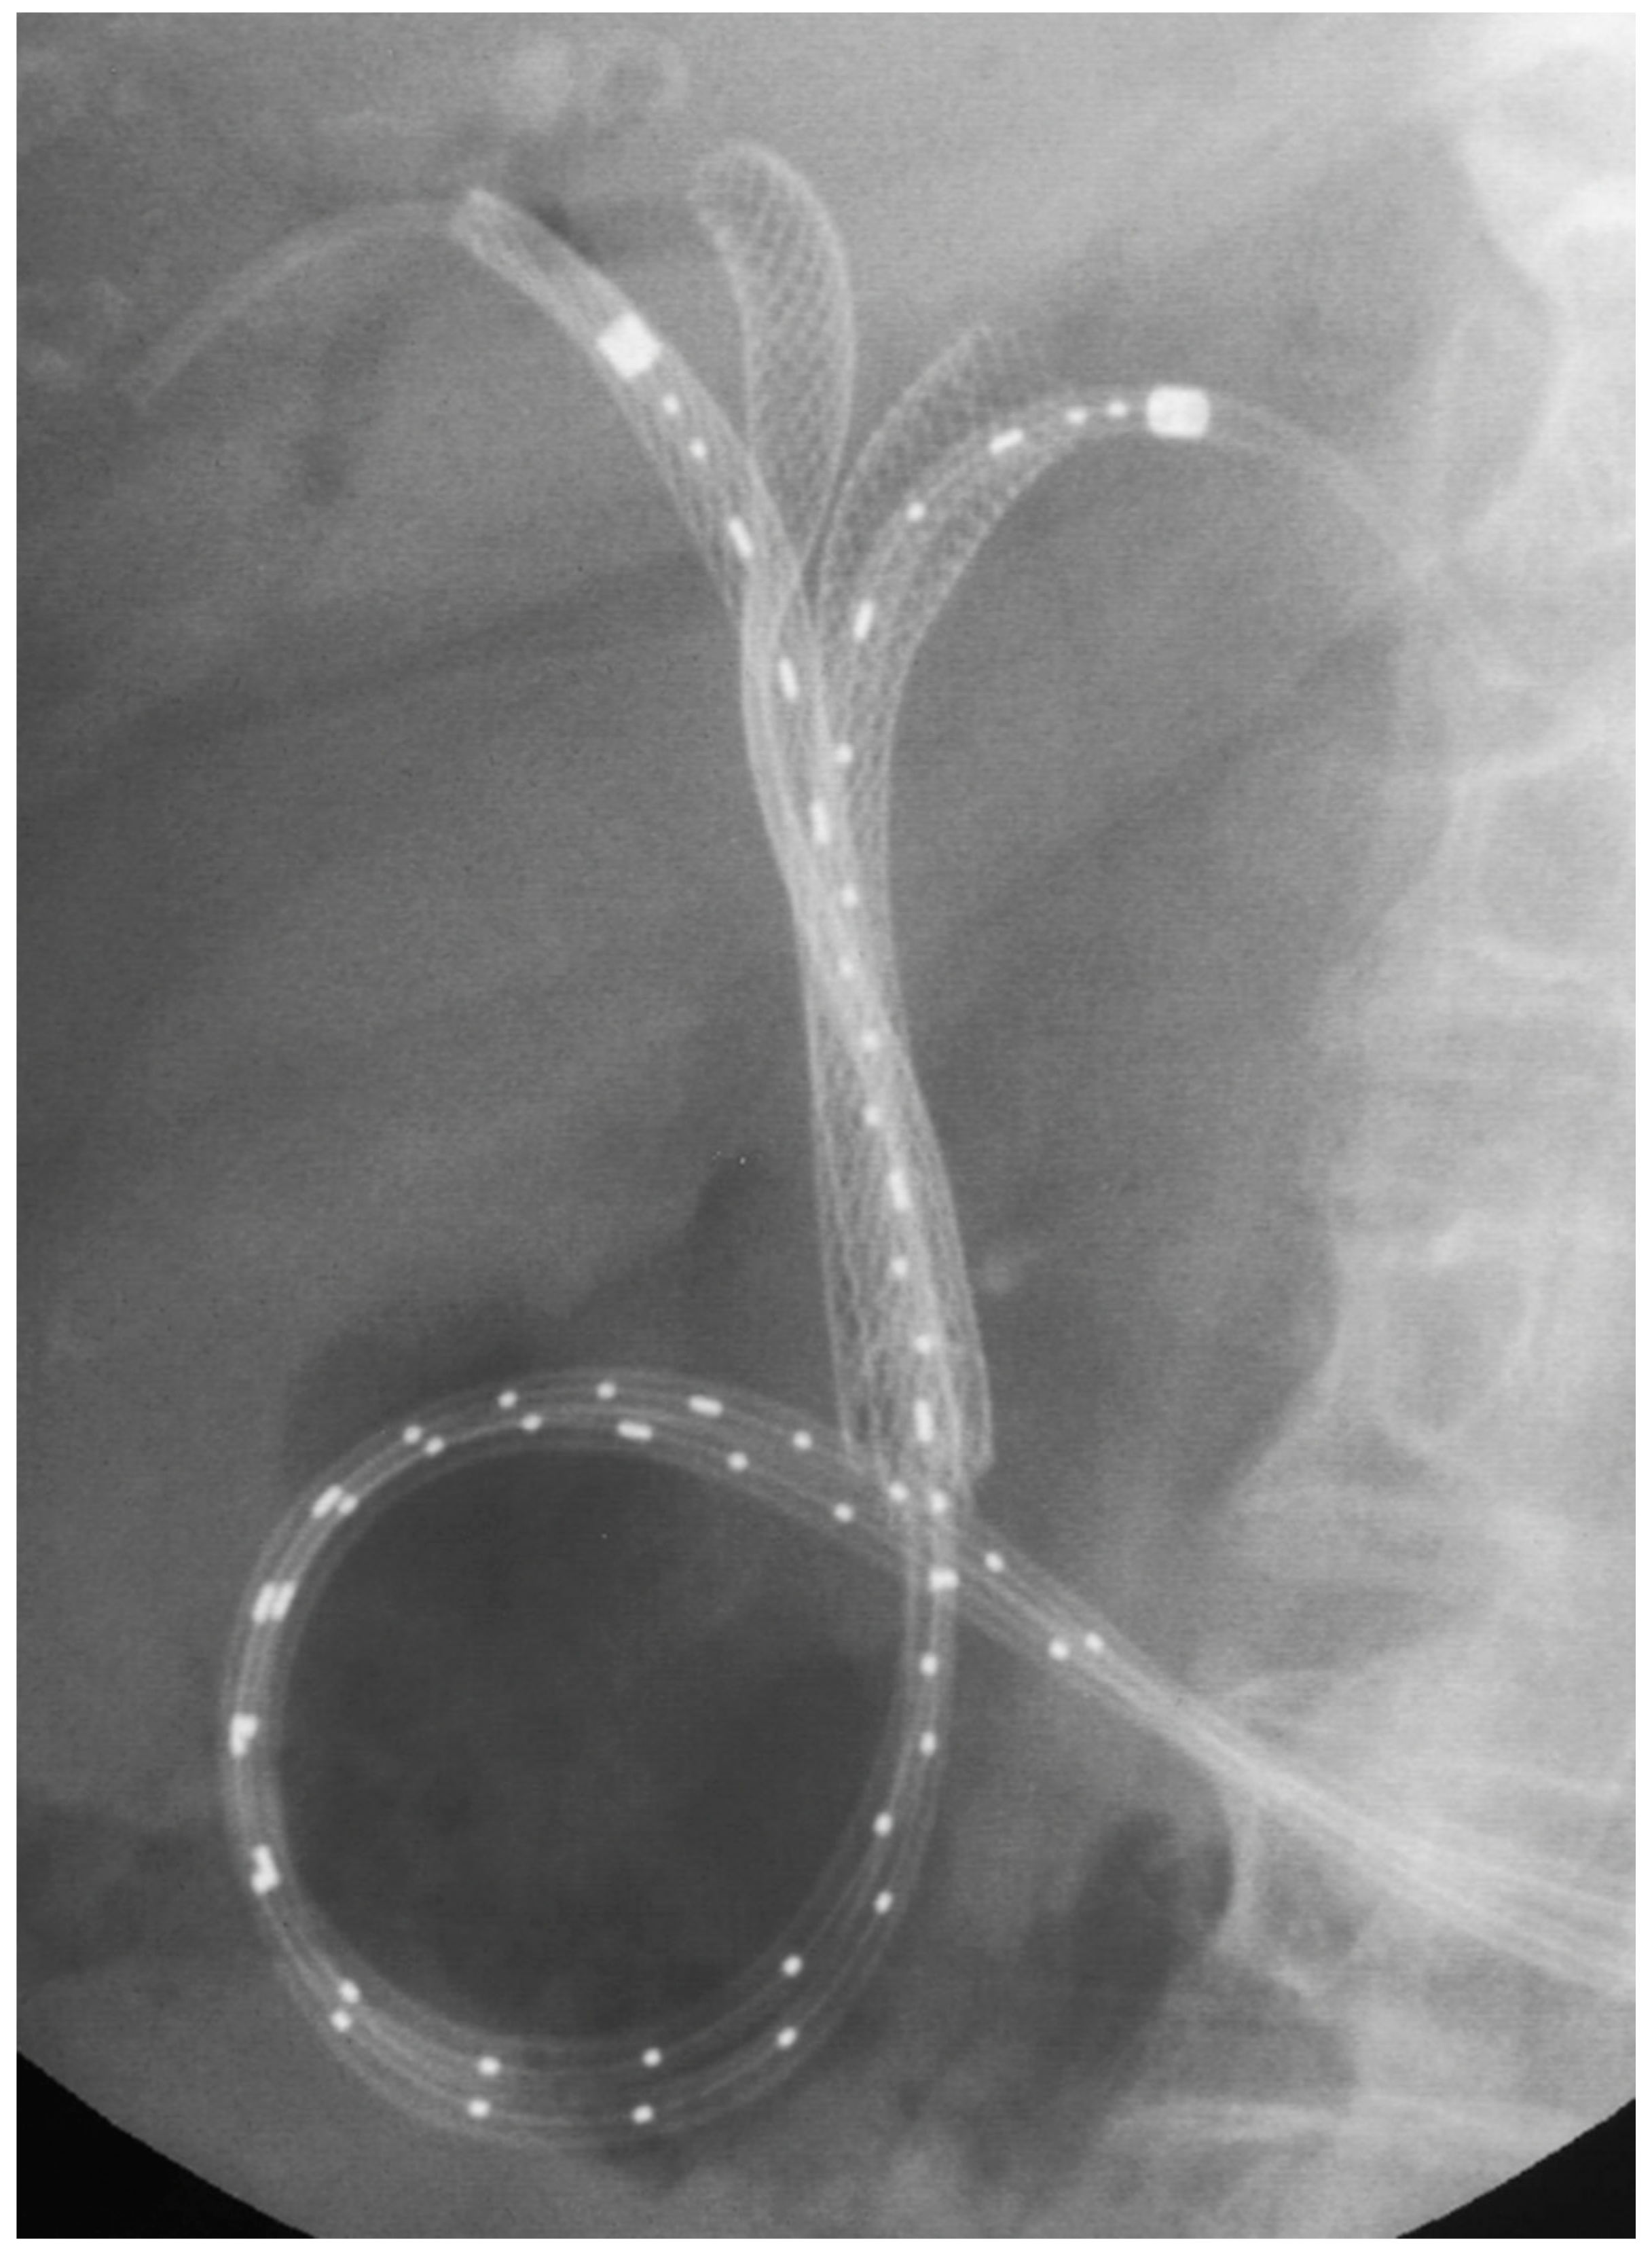

- Boškoski, I.; Tringali, A.; Familiari, P.; Bove, V.; Landi, R.; Attili, F.; Perri, V.; Onder, G.; Mutignani, M.; Costamagna, G. A 17 years retrospective study on multiple metal stents for complex malignant hilar biliary strictures: Survival, stents patency and outcomes of re-interventions for occluded metal stents. Dig. Liver Dis. 2019, 51, 1287–1293. [Google Scholar] [CrossRef] [PubMed]

- Naitoh, I.; Hayashi, K.; Nakazawa, T.; Okumura, F.; Miyabe, K.; Shimizu, S.; Yoshida, M.; Yamashita, H.; Ohara, H.; Joh, T. Side-by-Side versus Stent-in-Stent Deployment in Bilateral Endoscopic Metal Stenting for Malignant Hilar Biliary Obstruction. Dig. Dis. Sci. 2012, 57, 3279–3285. [Google Scholar] [CrossRef] [PubMed]

- Lee, T.H.; Moon, J.H.; Choi, J.-H.; Lee, S.H.; Lee, Y.N.; Paik, W.H.; Jang, D.K.; Cho, B.W.; Yang, J.K.; Hwangbo, Y.; et al. Prospective comparison of endoscopic bilateral stent-in-stent versus stent-by-stent deployment for inoperable advanced malignant hilar biliary stricture. Gastrointest. Endosc. 2019, 90, 222–230. [Google Scholar] [CrossRef] [PubMed]

- Kim, K.M.; Lee, K.H.; Chung, Y.H.; Shin, J.U.; Lee, J.K.; Lee, K.T.; Shim, S.G. A comparison of bilateral stenting methods for malignant hilar biliary obstruction. Hepatogastroenterology 2012, 59, 341–346. [Google Scholar] [CrossRef]

- Lee, T.H.; Moon, J.H.; Park, S. Biliary stenting for hilar malignant biliary obstruction. Dig. Endosc. 2020, 32, 275–286. [Google Scholar] [CrossRef] [PubMed]